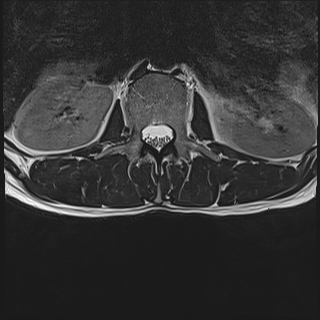

I had an MRI 12 days after the initial onset. This showed a slight disc bulge and small fissure in the disc (L4).

I wouldn't go back to the gym, well that's my opinion. You've obviously had a slipped disc (incidentally, it looks like the L5-S1 disc from the scan but I don't have all the views), and it takes a good deal more than a month to heal once the bulge has been reduced. The chances of a second slip are great at this stage. Be careful.